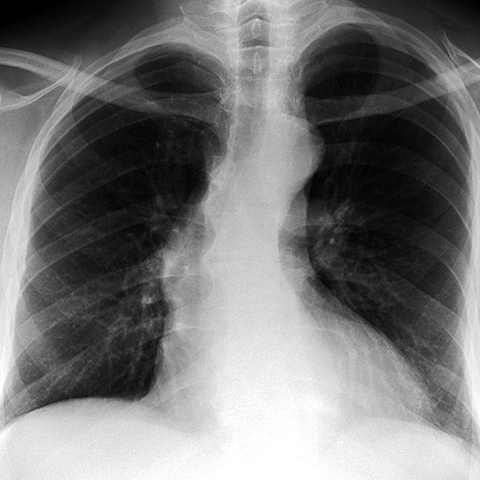

Aortic Stenosis [1 of 2]